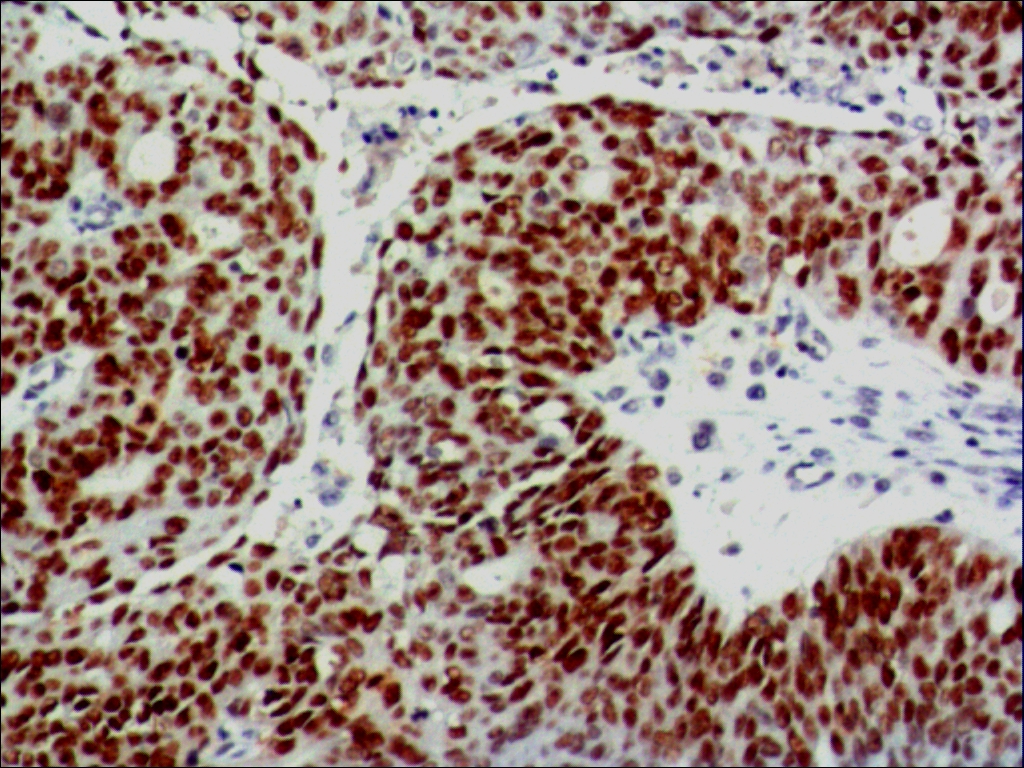

| 阳性部位: | 细胞核 |

| 阳性对照: | 乳腺癌 |

| 特异性 : | 此抗体与人来源的野生型和突变型p53反应,其它种属未检测。 |

| 推荐效价: | •原液使用前应以适当比例稀释 推荐稀释度为1:100~1:200 •工作液不必稀释,直接滴加使用 |